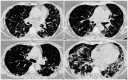

Case of Severe Treatment-Resistant Cryptogenic Organizing Pneumonia

Cryptogenic organizing pneumonia is a rare interstitial lung disease with different onset of symptoms, which responds rapidly to glucocorticoid treatment. We present a case of cryptogenic organizing pneumonia which manifested as a progressive 3-year dyspnea that ultimately has led to acute respiratory failure. Moreover, treatment with prednisone for this patient exhibited slow onset of the effect.